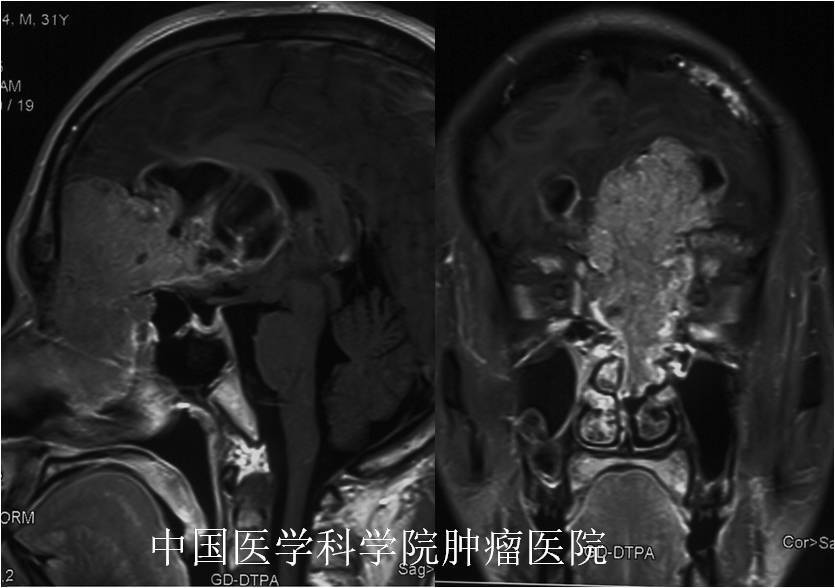

开颅手术切除颅内外广泛沟通的巨大嗅神经母细胞瘤,挽救患者生命